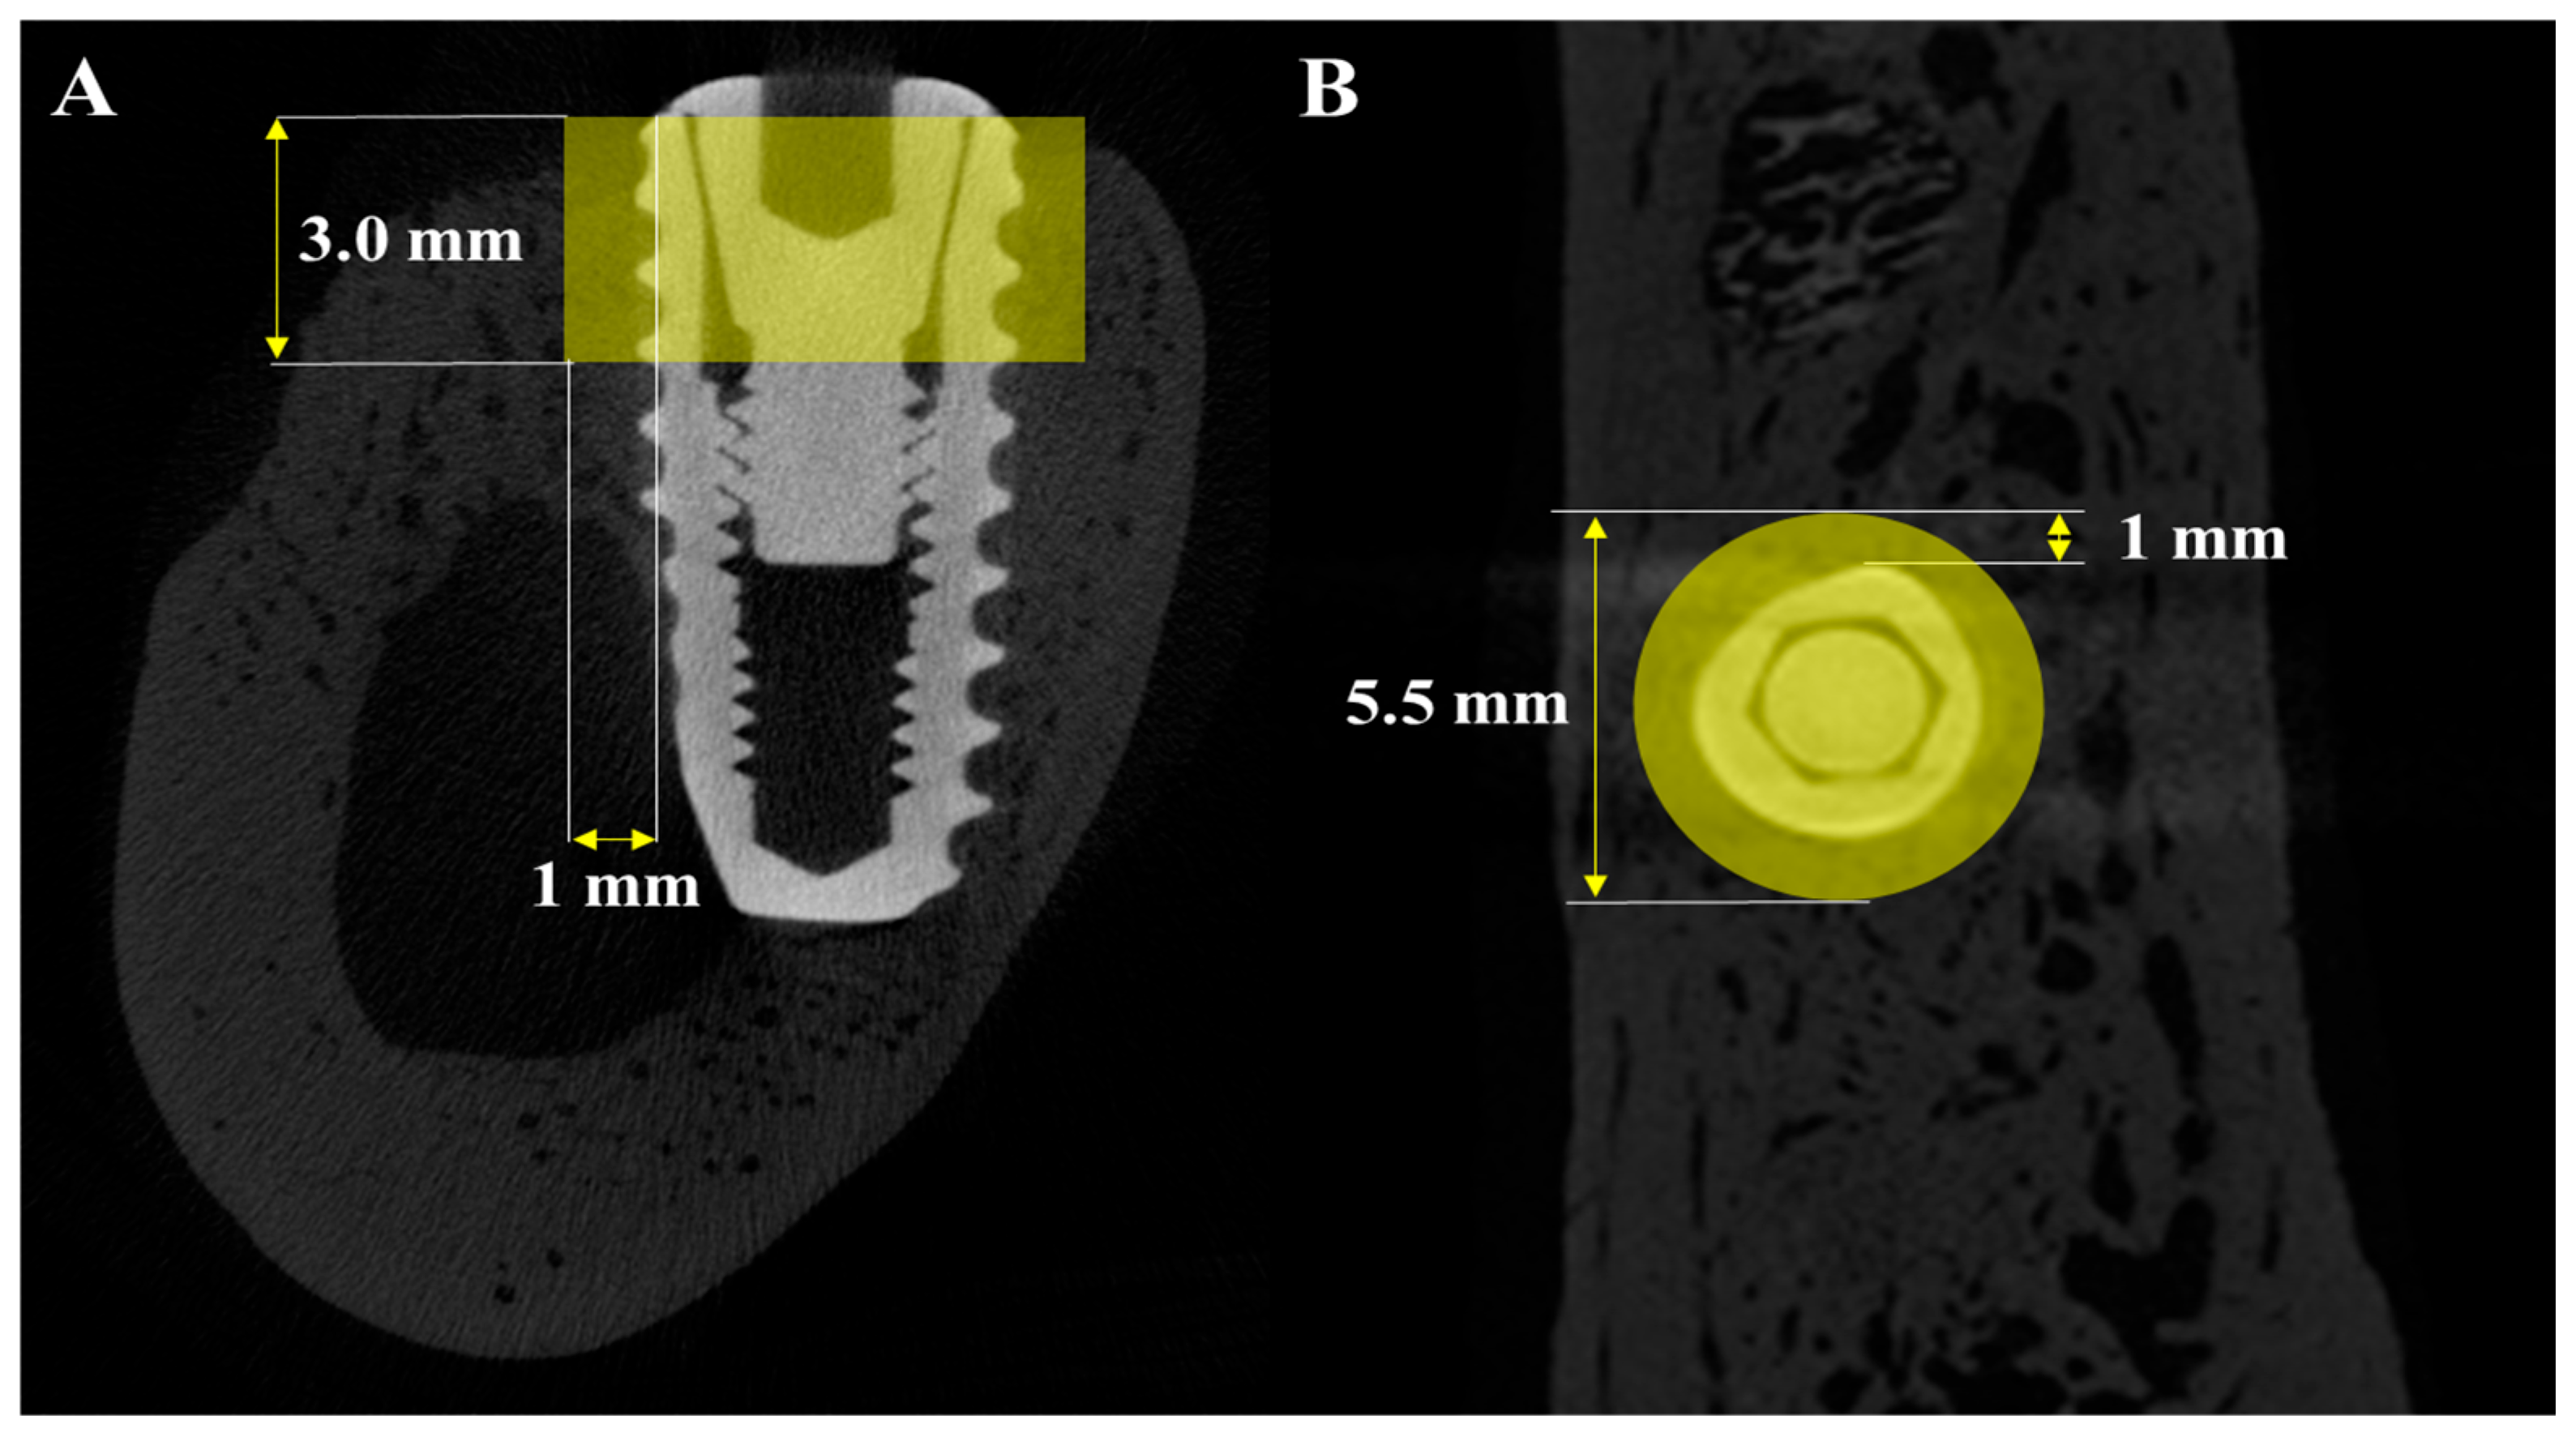

2.2.4. Volumetric Analysis Using Medical Computed Tomography (Medical CT)

2.2.5. Volumetric Analysis Using Micro-Computed Tomography (μ-CT)